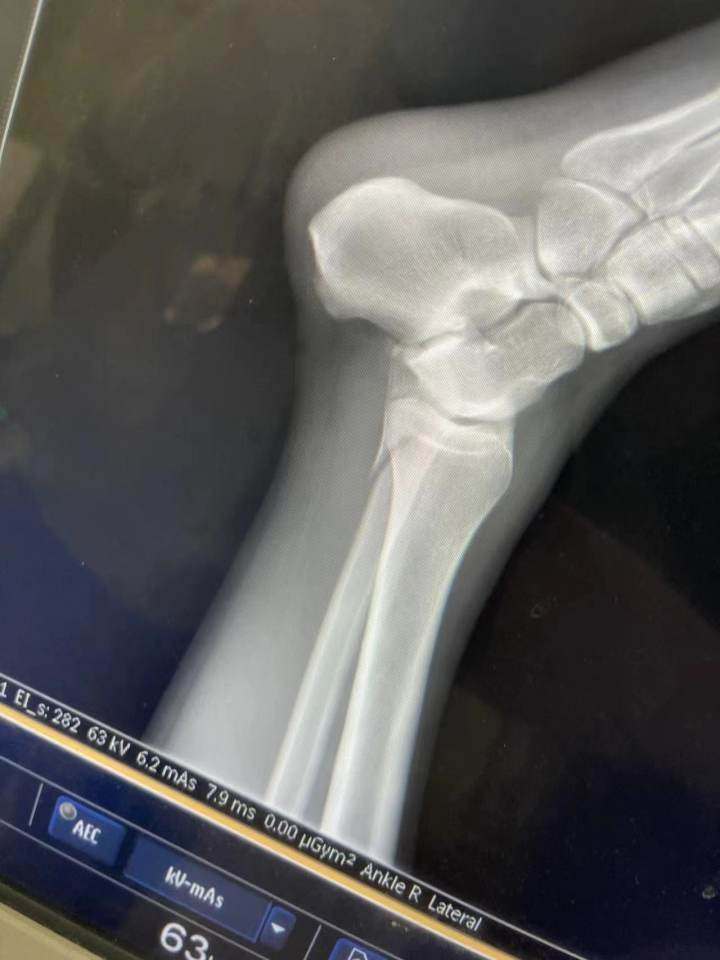

“医生诊断,我腿上的胫骨腓骨同时断裂。从场地送到医院救护车的钱,都是我和小董一人一半自己付费的,连治疗费用都是我们自己垫付的。”